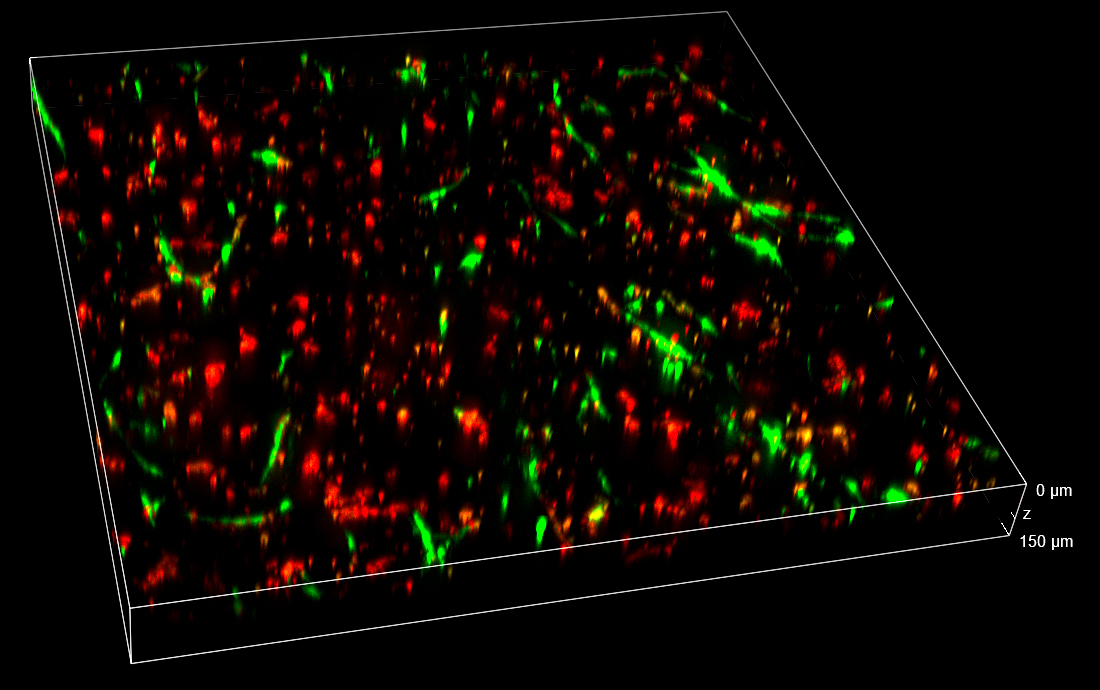

In the Figure 2, the full field of view (FOV) in XYZ dimensions collected 24 h post-treatment is shown. Thanks to the 25 mm diagonal FOV of the camera and to the ability to penetrate inside the sample without losing the spinning disk confocality, it was possible to visualize and record cells that homogeneously colonize the entire thickness of the 3D matrix.

Figure 2. 3D view of the entire FOV acquired with spinning disk at 24 h post-treatment. FOV with XY=4422×4422 µm, Z=530 µm. 3D matrix thickness was entirely acquired. Tumor target A673 cells are shown in red and AD-MSCs TRAIL in green.

Data obtained from live monitoring of co-cultures in VITVO were compared with end-point readouts from fixed samples at specific time points post-treatment (24 and 72 h, Figure 8). 3D comparison among three different FOVs confirmed a homogeneous distribution of cells without any significant inter-field difference. These data point out that AD-MSCs TRAIL were persisted over time, instead of A673 tumor cells which massively decreased in their signal and cell density (Figure 8).

Figure 8. Z-stacks on VITVO FOVs collected and fixed at different time points with spinning disk. 3 different FOVs corresponding to 24 h and 72 h post-treatment fixed sample, respectively (10x objective magnification).